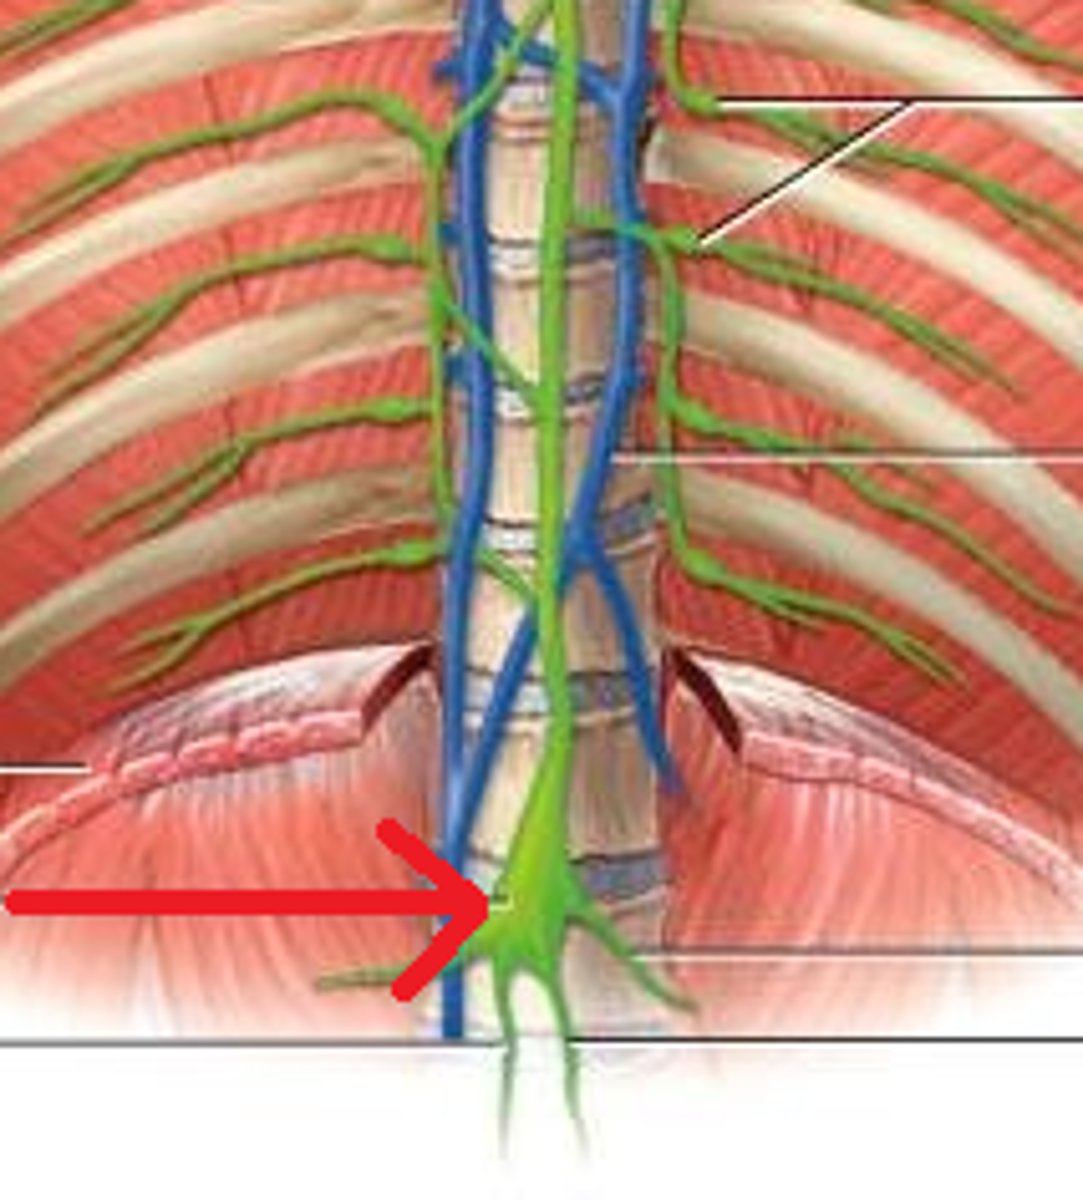

Cisterna chyli